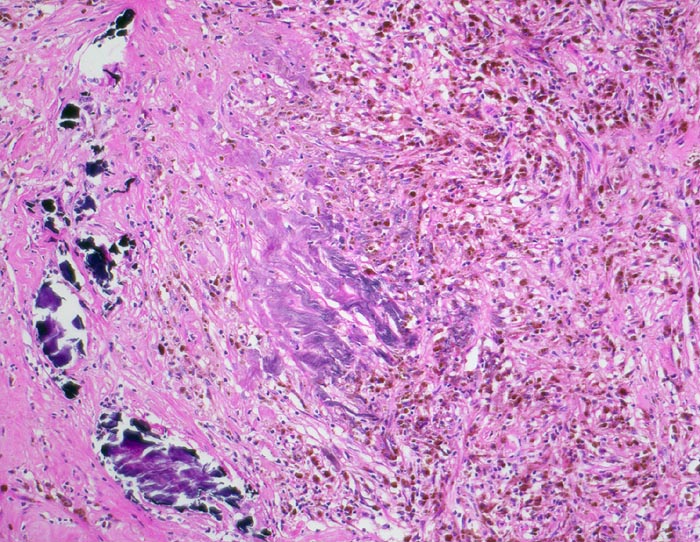

PathoPic – image database / PathoPic ID 4891 - hellzelliges Nierenzellkarzinom: Stromaverkalkungen und Einblutungen

hellzelliges Nierenzellkarzinom: Stromaverkalkungen und Einblutungen

Sklerosiertes Stroma mit grobscholligen dystrophen Verkalkungen und Blutungsresiduen in Form von hämosiderinbeladenen Makrophagen (braune Zellen in der rechten Bildhälfte).

8cm grosser Tumor im Nierenoberpol. Bunte Schnittfläche mit multiplen gelben Knoten, ödematösem Stroma und Einblutungen, sowie fokaler Zystenbildung. Der Tumor infiltriert das Nierenbecken. Die Vena renalis ist tumorfrei.